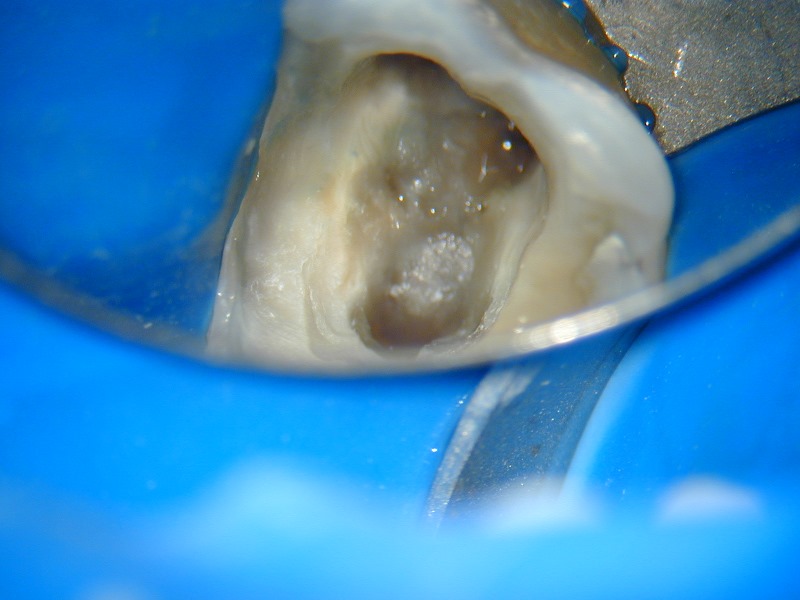

O microscópio operatório para odontologia foi desenvolvido para que pudéssemos ter a visibilidade necessária para detectarmos a entrada dos canais radiculares que recobertos por dentina ou por detritos nos impediam a completa descontaminação dos canais radiculares. Com ele também visualizamos e amplificamos a imagem para detectar possíveis trincas, fraturas ou calcificações que impedem o tratamento. Observem as fotos dos casos clínicos que mostram como conseguimos trabalhar e fotografar os casos com a máquina acoplada ao MO.

Localização e tratamento de perfuração na entrada do canal Mésio Vestibular.